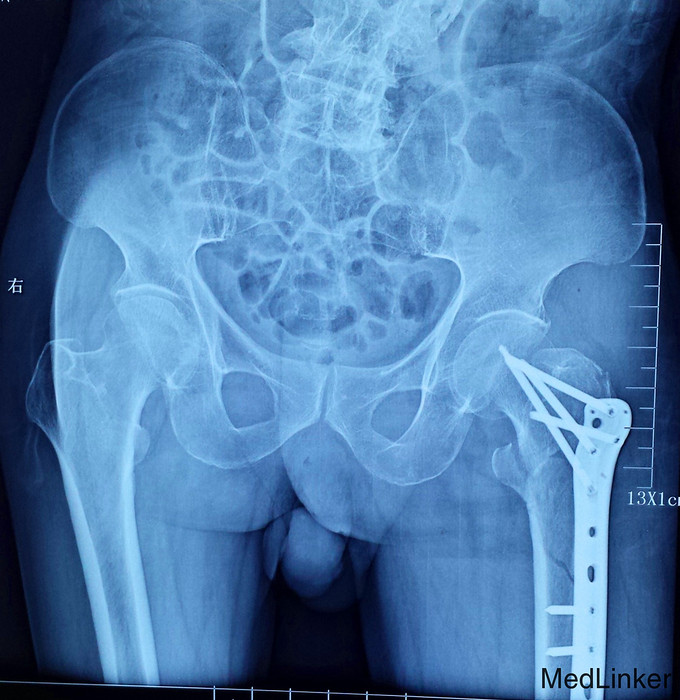

患者,男性,75岁,意外摔倒。右腿活动受限1小时入院。

X光片提示,患者在摔倒时,右腿发生了粗隆间合并粗隆下骨折。各项指标均符合,先进行了两天的静脉消炎注射,第三天进行了手术,手术顺利。

为了降低粗隆间骨折所带来的长期卧床所致的并发症几率,减少病人的死亡率,应尽快使病人坐起、翻身、下床活动,而要达到上述目的,往往需要借助于手术使骨折得到复位、固定。也就是说,在老人身体耐受的情况下,应尽量争取手术的机会。术后尽量为病人创造康复锻炼的基本条件,最大限度的改善患肢功能,以使老人早日恢复生活自理能力,改善生活质量。并且要特别注重补钙治疗,以预防老年人因骨质疏松而带来再次的骨折,